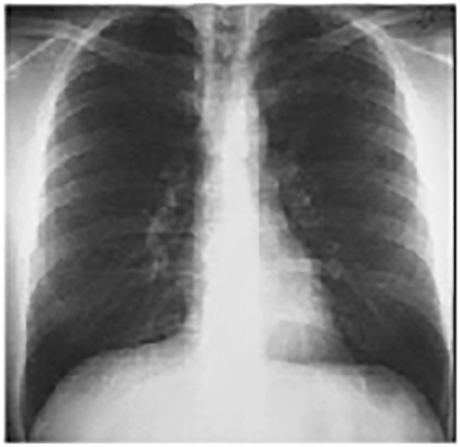

PA and Lateral

Click on the Xrays to enlarge them.

Choose the best interpretation of the chest X rays:

Straight back

Entirely normal

Rib notching

Right-sided aortic arch

Dextrocardia